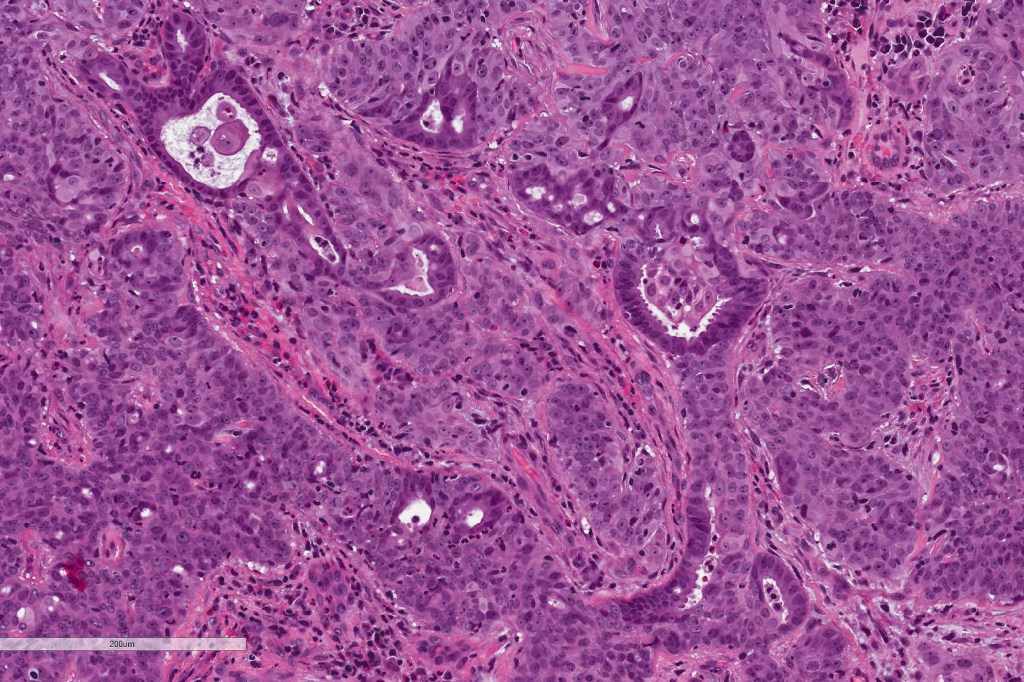

Histological features

•Broad anastomosing epithelial trabeculae

•Variable necrosis (may be comedo-like)

•Ducal differentiation invariably present

•Squamous differentiation